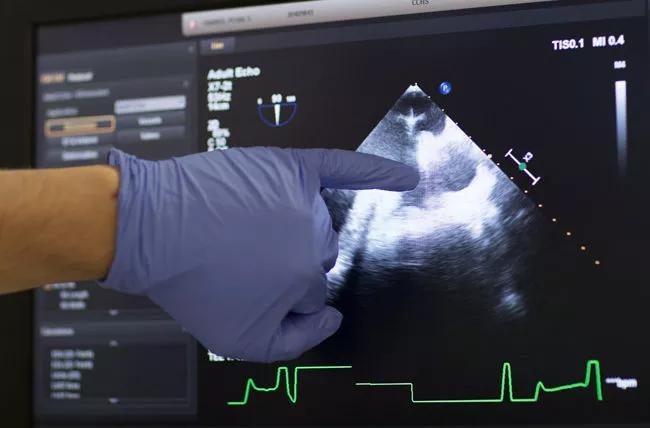

Cardiac injuries, particularly left ventricular systolic dysfunction, are a common consequence of hematopoietic stem cell transplantation (HSCT) during childhood and adolescence.

But guidelines and clinical protocols vary regarding the need, frequency and duration of post-transplant echocardiographic screening in long-term survivors.

New research by a team including Cleveland Clinic Children’s pediatric hematologist/oncologist Seth Rotz, MD, shows that HSCT survivors who are asymptomatic and didn’t undergo total-body irradiation or anthracycline-based chemotherapy are unlikely to have systolic dysfunction. As a result, these patients probably don’t need surveillance echocardiograms, unless otherwise indicated, after the first few years post-transplantation, the researchers conclude.

Dr. Rotz and his colleagues sought to identify the rate of abnormal systolic function in survivors at least five years post-infusion, and to determine if a subset of survivors could safely avoid future echocardiographic screening.

The researchers analyzed the echocardiograms for ejection fraction (EF — historically, the metric for left ventricle function) and left ventricular measurements, which they converted to age-adjusted z-scores.